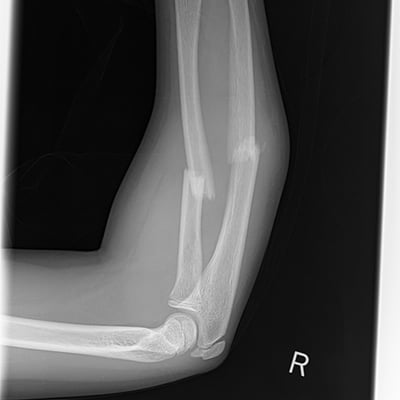

This module will help you achieve optimal images when performing elbow, humerus, shoulder, and scapula examinations. Patient preparation and positioning are discussed, as well as technical settings and patient instructions. Descriptions and images of the expected anatomical structures are included, as well as image evaluation criteria.